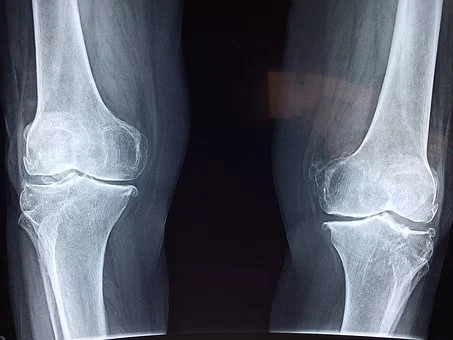

뉴질랜드에 사는 마오리족을 비교 분석한 결과 해안가에 거주하면서 초록입홍합을 즐겨 먹는 사람은 그렇지 않은 사람에 비해 관절염에 걸린 비율이 매우 낮았다고 합니다.

이후로 초록입홍합은 관절약에 특효로 알려져 왔습니다.

초록입홍합 오일을 가지고 동물 실험으로 관절 손상도를 테스트한 결과

초록입홍합 오일을 복용한 실험군에서 관절 손상도가 현저히 낮아지는 연구 결과를 보였다고 합니다.

국내 7개 대학병원에서 임상시험도 진행했는데요.

초록입홍합 추출 오일을 1개월 투여하자 57%의 관절 기능이 개선되는 결과를 보였다고 합니다.

2개월 이후에는 83%의 개선 효과를 보였다고 하니 초록입홍합이 관절에 미치는 긍정적인 영향은 의심하지 않으셔도 되겠습니다.